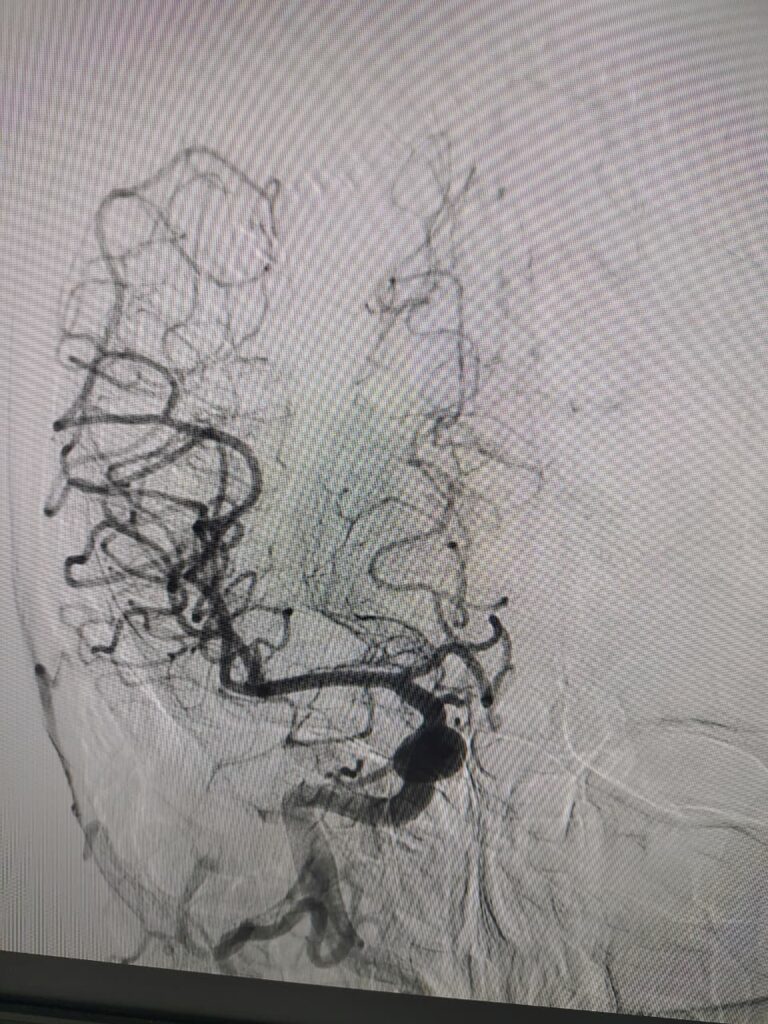

Ruptured Brain aneurysm (left ICA communicating segment wideneck aneurysm) treated with Stent Assisted Coiling.

Coiling in live case